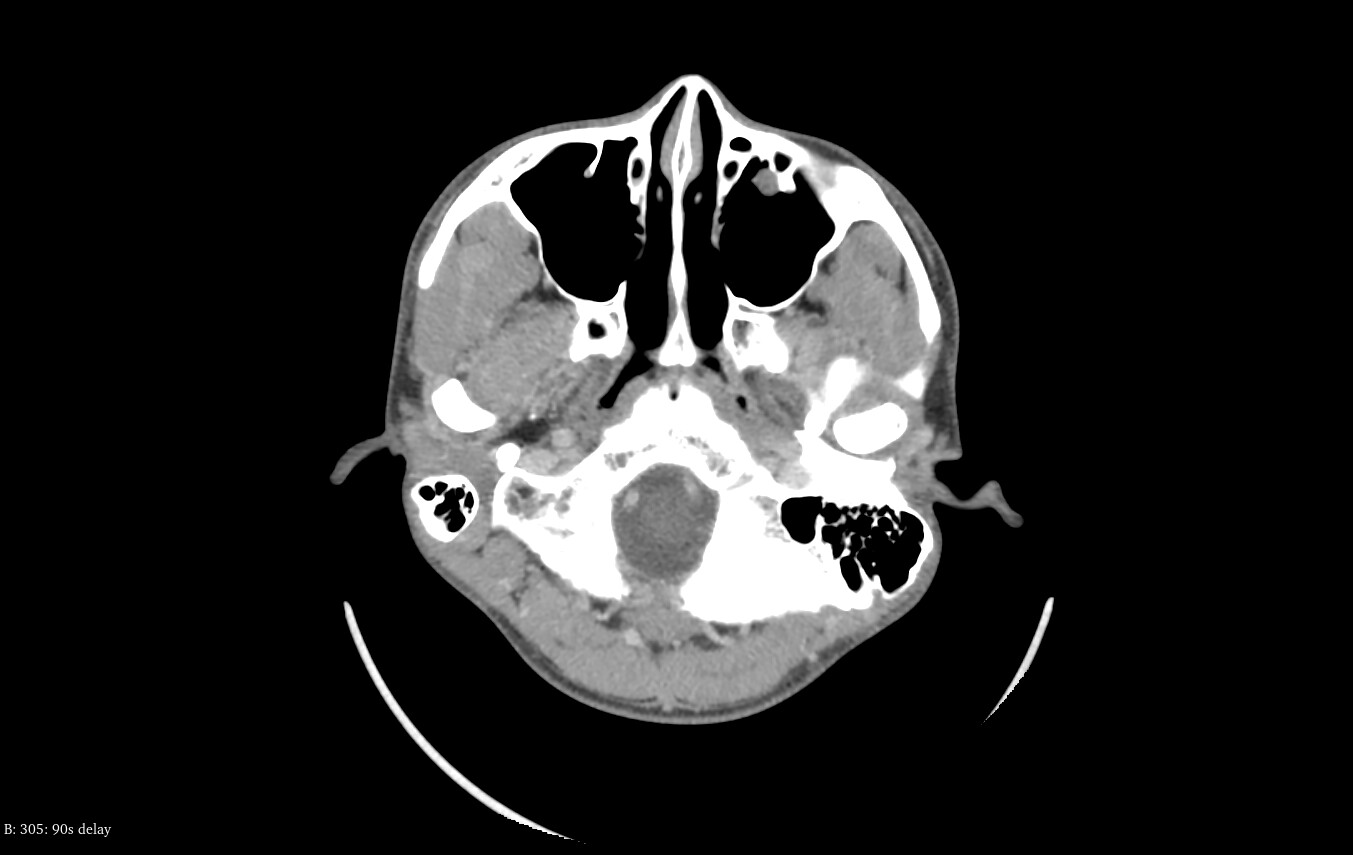

After researching, I realized they had not scanned the veins, so I initially suspected Bow Hunter’s syndrome, but later realized that wasn’t the case and felt hopeless. Soon afterward, I learned about Eagle syndrome and jugular vein compression, and last month I underwent CTA and CTV simultaneously.

An ENT doctor told me there was no abnormality, but I think I can see signs of venous compression myself. I also have atrial fibrillation, and when I bend my head downward, it feels like it places a burden on my heart. The symptoms similar to Horner’s syndrome have disappeared, but the diplopia still remains. In the early stages, I also experienced dizziness when turning my head, but that symptom has since resolved.

I don’t know whether my left-sided torticollis is the cause or the result, but it seems that the left C1 is larger and angled more downward. The styloid process is not particularly elongated, but perhaps because of the torticollis, the angle looks problematic.